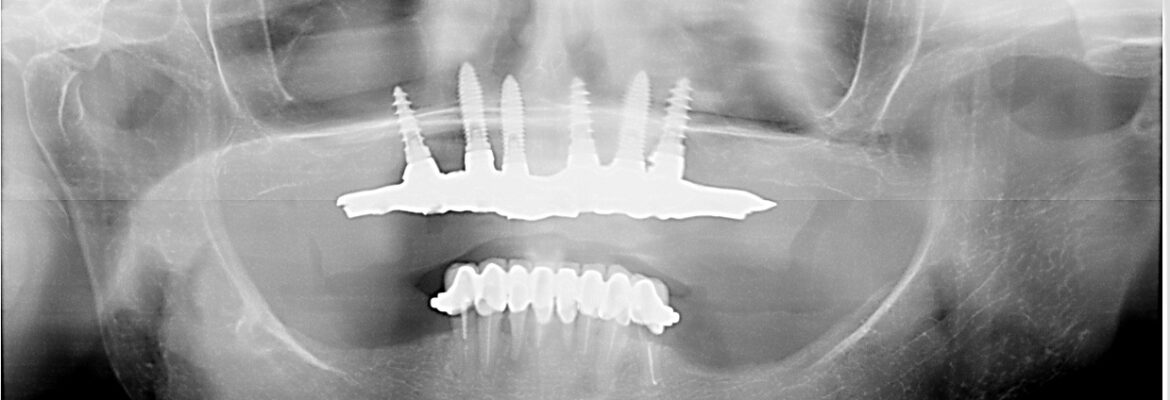

Décider de réaliser ces soins dentaires, un implant dentaire ou une prothèse dentaire en Espagne est une démarche qui s’est largement banalisée depuis 2012. L’offre de soins en Espagne vous permet d’accéder à des traitements de qualité à prix raisonable avec une économie de 40 à 50% par rapport à l’offre française tout en gardant une excellente qualité de soin et de prise en charge.